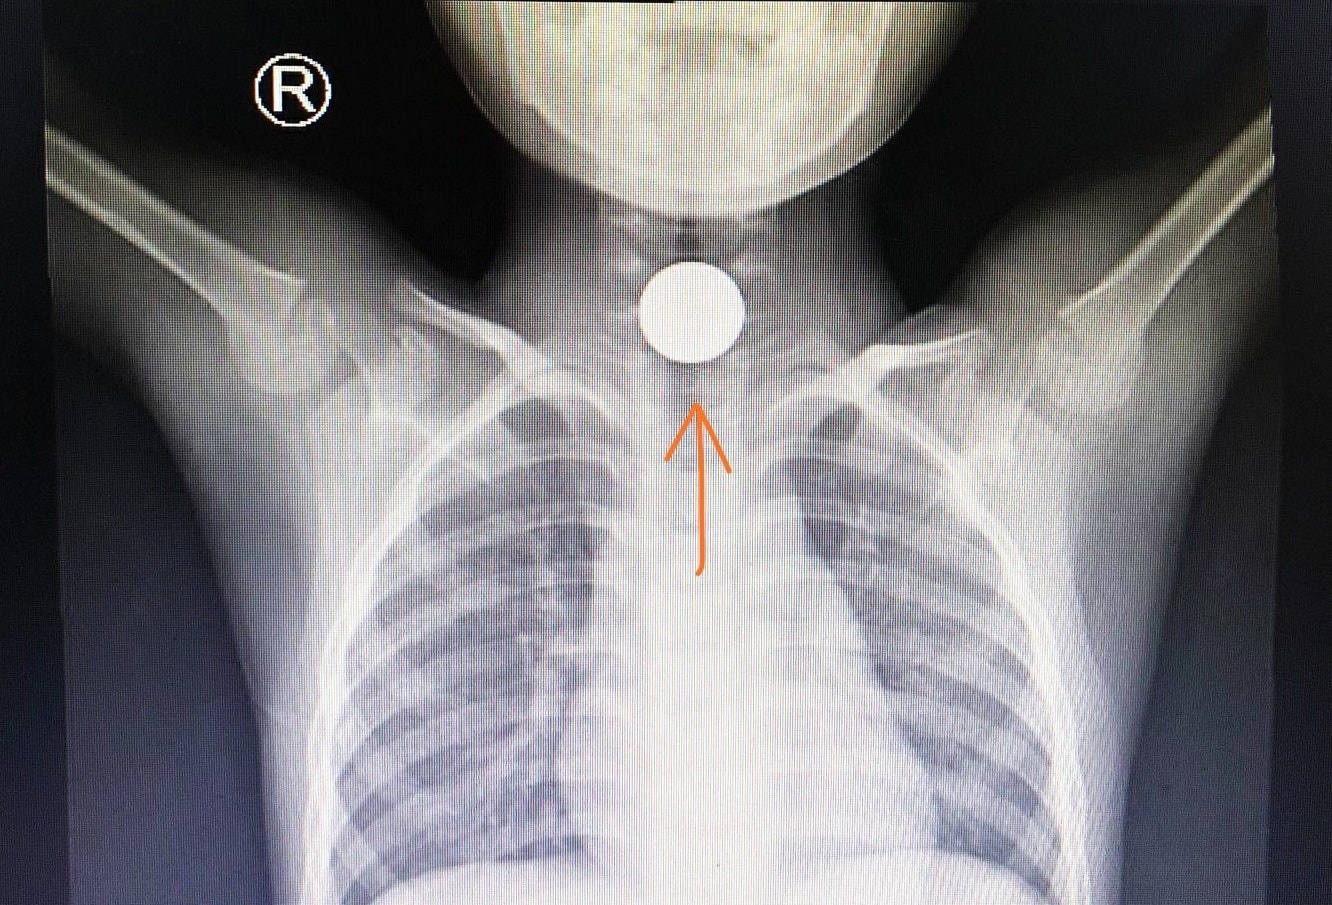

| Đồng xu kẹt trong thực quản cho một bệnh nhi 5 tuổi. Ảnh: BVCC. |

Ngoài tai nạn giao thông, đơn vị này còn tiếp nhận và xử trí nhiều trẻ gặp tai nạn nuốt đồng xu, hóc hạt đậu, dị vật thực quản, phù phổi do ngã xuống ao, uống nhầm xăng, rượu, bỏng nước sôi.